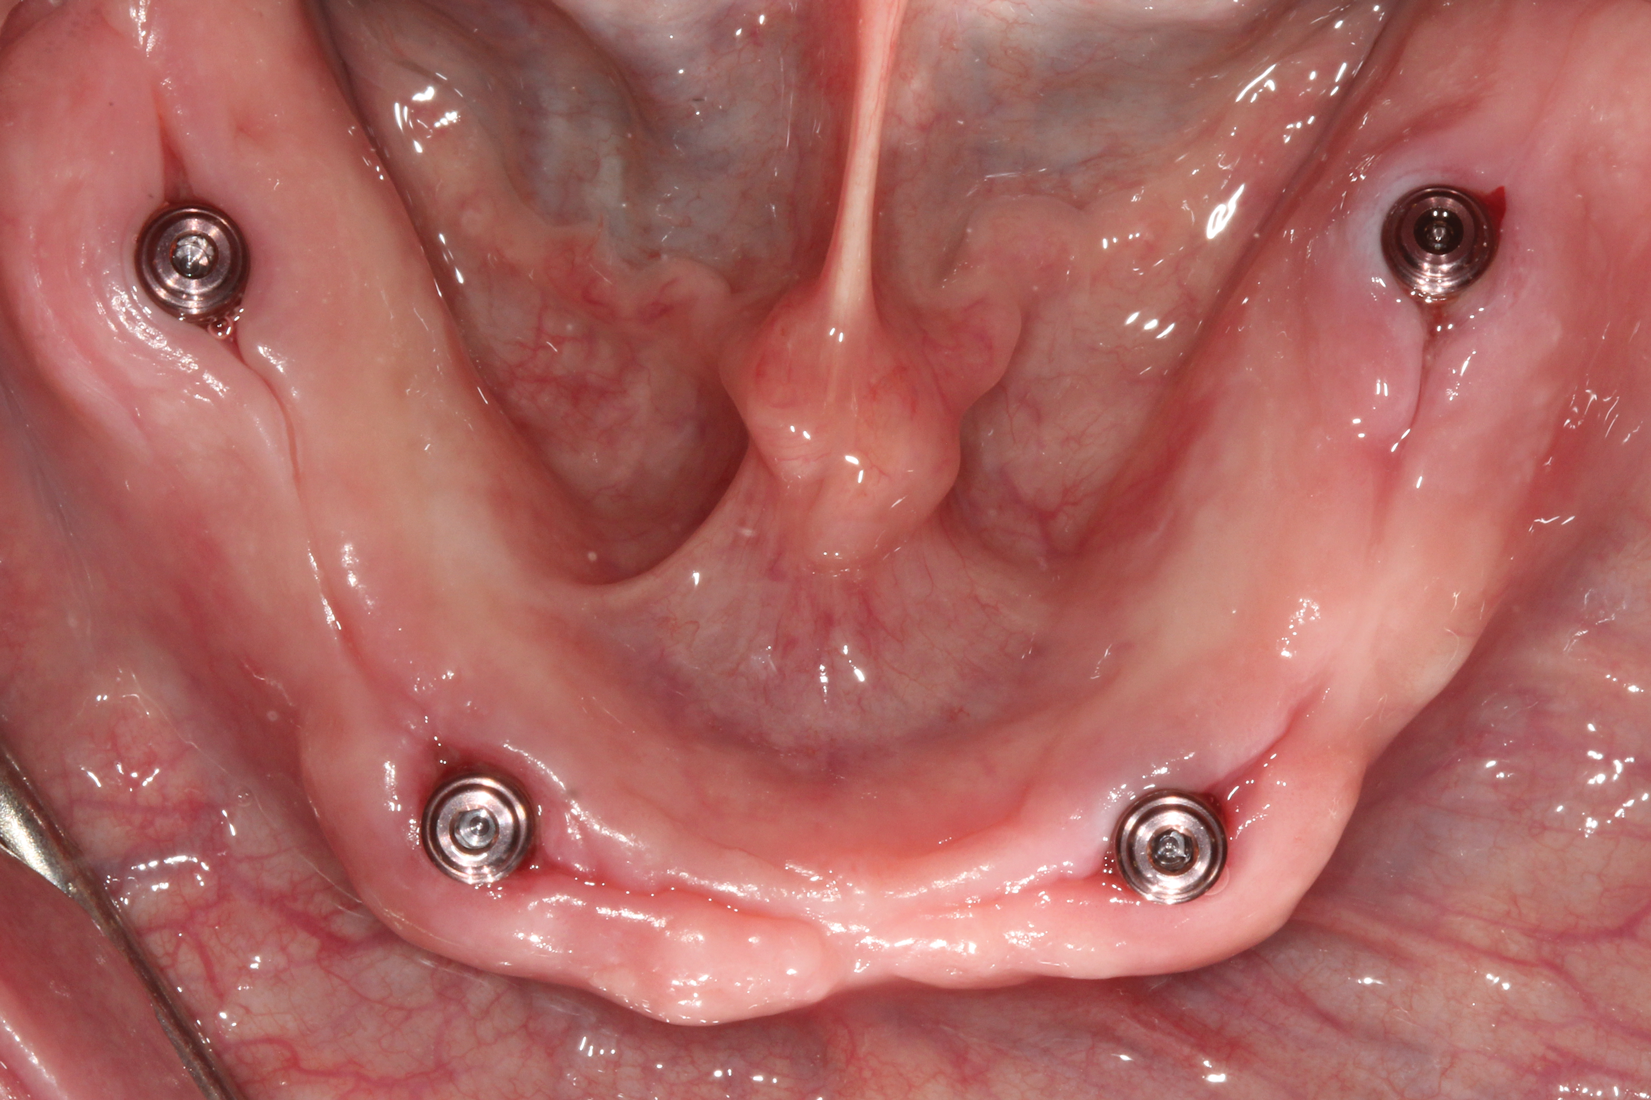

The patient returned and implants were assessed for integration and implant exposure procedures. A crestal incision was made and healing abutments were placed; at the time of uncovery, tissue measurements were made from the top of the implant platform to the superior portion of the tissues. Two weeks later, the patient returned and overdenture abutments (LOCATOR® R-Tx, Zest Dental Solutions, [alternatively: ERA, Sterngold; Hader, Preat]) in tissue heights corresponding to the measured tissue depths were placed (Figure 4 and Figure 5). After placement of the abutments, a panoramic radiograph was made to confirm complete adaptation of the abutments to the dental implants (Figure 6).Abutments were torqued to manufacturer's recommended torque values and denture housings were placed on top of each abutment (Figure 7). Optical scans of the maxillary and mandibular arches were made using the intraoral impression scanner. The patient's existing denture was relieved and relined with a silicone-based soft reline material (CHAIRSIDE® Soft, Zest Dental Solutions, [alternatively: Coe-Soft, GC America; Ufi Gel SC, Voco]). The intaglio and cameo surfaces of the maxillary and mandibular prostheses were optically scanned using the intraoral scanner.

Fig 5. Mandibular overdenture abutments were placed. Fig 5. Mandibular overdenture abutments were placed.

Figure 5